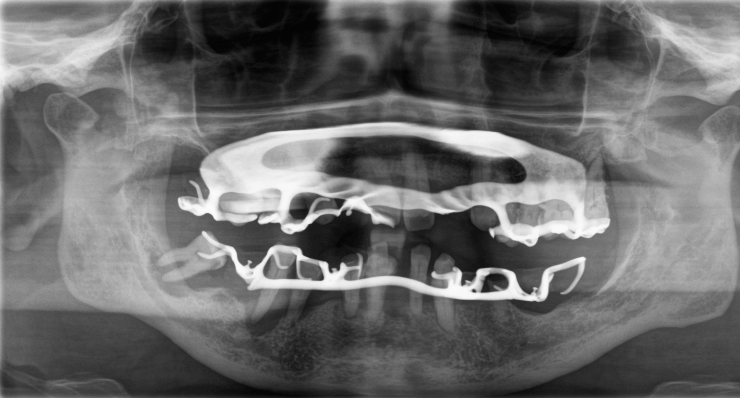

Biss nach PZR

Entzündungen und Rezessionen sind deutlich erkennbar.

Die Prothesen waren durch Zahnsteinverblockungen und Gingivahyperplasien nicht mehr herausnehmbar.